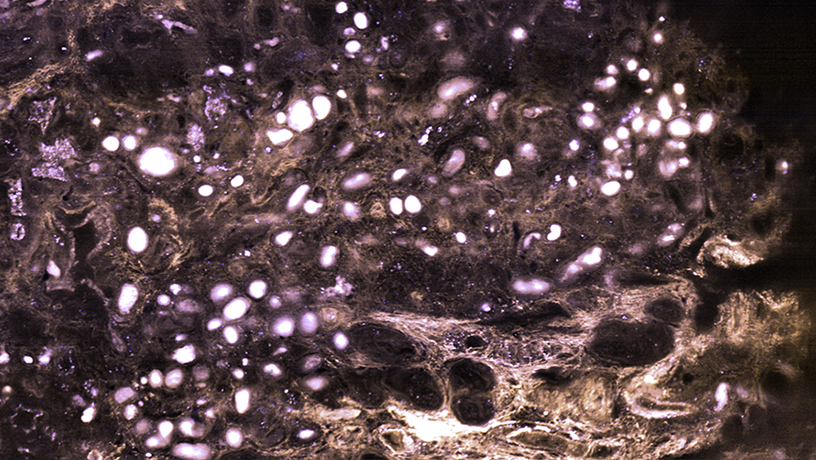

MediSCAPE imaging of fresh human kidney compared to gold standard periodic acid-Schiff (PAS) histology of the same tissue. Center shows large area scanned using MediSCAPE. Panels point to specific features of the kidney that are either normal or represent disease. 488 nm excited autofluorescence is color-coded in a yellow-blue scale. “One of the first tissues we looked at was fresh mouse kidney, and we were stunned to see gorgeous structures that looked a lot like what you get with standard histology,” says Kripa Patel, a recent PhD graduate from the Hillman lab and lead author of the study. “Most importantly, we didn’t add any dyes to the mouse —everything we saw was natural fluorescence in the tissue that is usually too weak to see. Our microscope is so efficient that we could see these weak signals well, even though we were also imaging whole 3D volumes at speeds fast enough to rove around in real time, scanning different areas of the tissue as if we were holding a flashlight.”